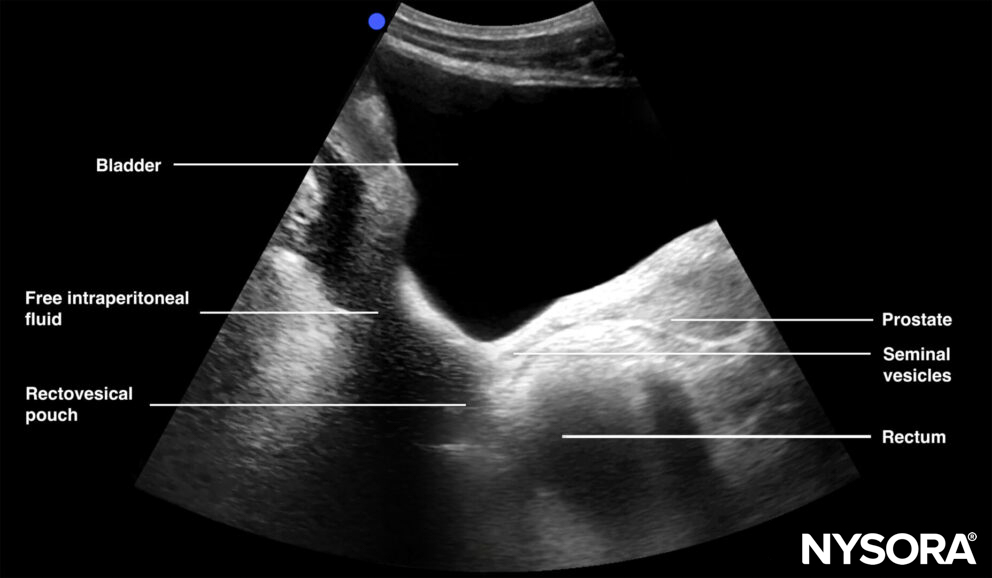

Sonoanatomy of interest in males:

Longitudinal view of the male pelvis with free fluid in the rectovesical pouch after Foley catheter insertion.

Pelvic free fluid collects behind the bladder or the area lateral to the bladder (rectovesical pouch in men and the rectouterine pouch or pouch of Douglas in women).

Sagittal section through the pelvis with free fluid in the rectovesical pouch in men and the rectouterine pouch (pouch of Douglas) in women.